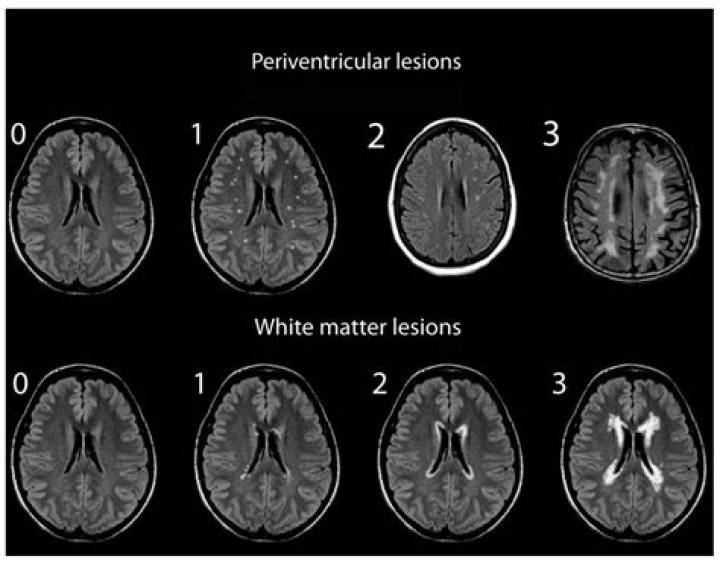

Multiple studies have found that people with migraines have an increased risk of brain lesions. The two main types of lesions found in migraineurs include: White matter hyperintensities (WMH): These lesions appear bright white on certain sequences of MRI scans.

What are migraine spots on MRI?

What does migraine look like on an MRI? In some people with migraine, MRI scans of the brain may show white spots or areas. These are caused by lesions or irregular areas in the white matter of the brain. White matter tissue is deep in the brain and is mostly made up of nerves.